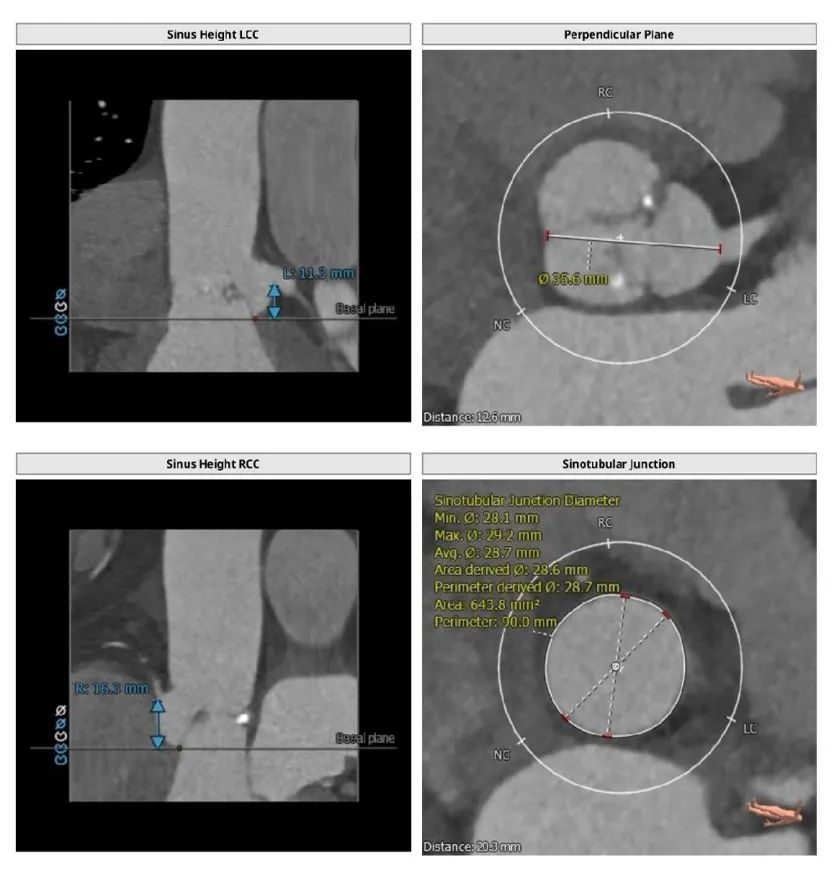

本例患者三叶瓣,重度钙化,左右冠瓣融合,病人瓣环25.2,左室流出道26.9,AL比值=0.93,法氏窦结构长短径均超过30,其中长径35.6,左右冠高度均超过12,瓣叶稍增厚,Stj28.7,距离虚拟瓣环平面23.3mm,综合解剖学因素,同时满足AL比值<0.96以及STJ高度≥23.8mm两个因素,发生瓣中瓣可能性极大。广东省医Tavr团队决定使用Numed25球囊预扩,预装VenusA29号瓣膜进行手术预案。

根部解剖: